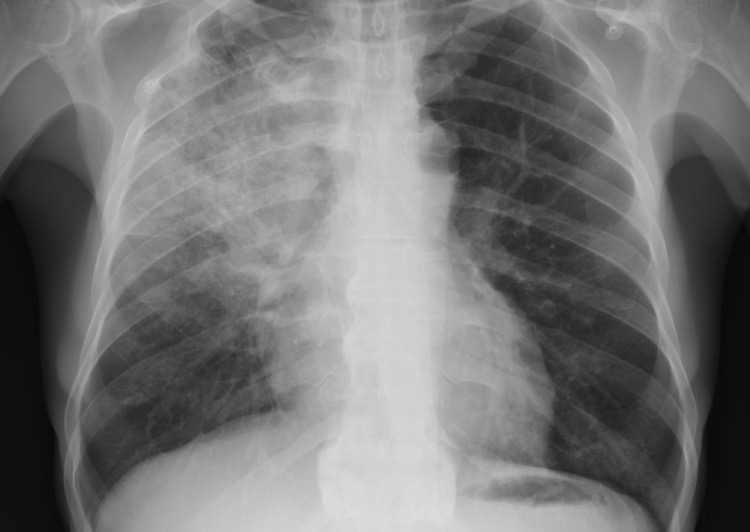

Диагностика

Когда женщины испытывают боли в области сердца, они чаще всего обращаются к терапевту или кардиологу. В зависимости от истории болезни и сопутствующих симптомов, диагностику и лечение могут проводить гастроэнтерологи, неврологи или пульмонологи. Для установления точного диагноза могут потребоваться следующие анализы и исследования:

- рентгенография;